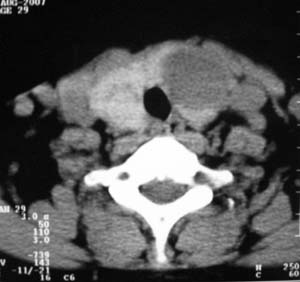

以下是引用zsl6918在2007-8-27 14:40:00的发言:[br]双侧甲状腺多发性低密度占位,边界清晰,密度欠均匀,尤以左侧明显,与周围组织分解清,考虑多发性腺瘤可能性大,不除外结节性甲状腺肿

以下是引用liaizhi在2007-8-27 15:20:00的发言:[br]双侧甲状腺散在多个囊性第密度影,左侧最大一个病灶与正常甲状腺分界尚可,气管受压稍右移。考虑甲状腺瘤的可能性大。